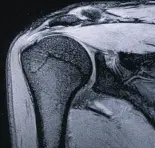

МРТ диагностика суставов, что дает расширенные возможности в установлении диагноза и в выборе тактики лечения.

МРТ плечевого сустава